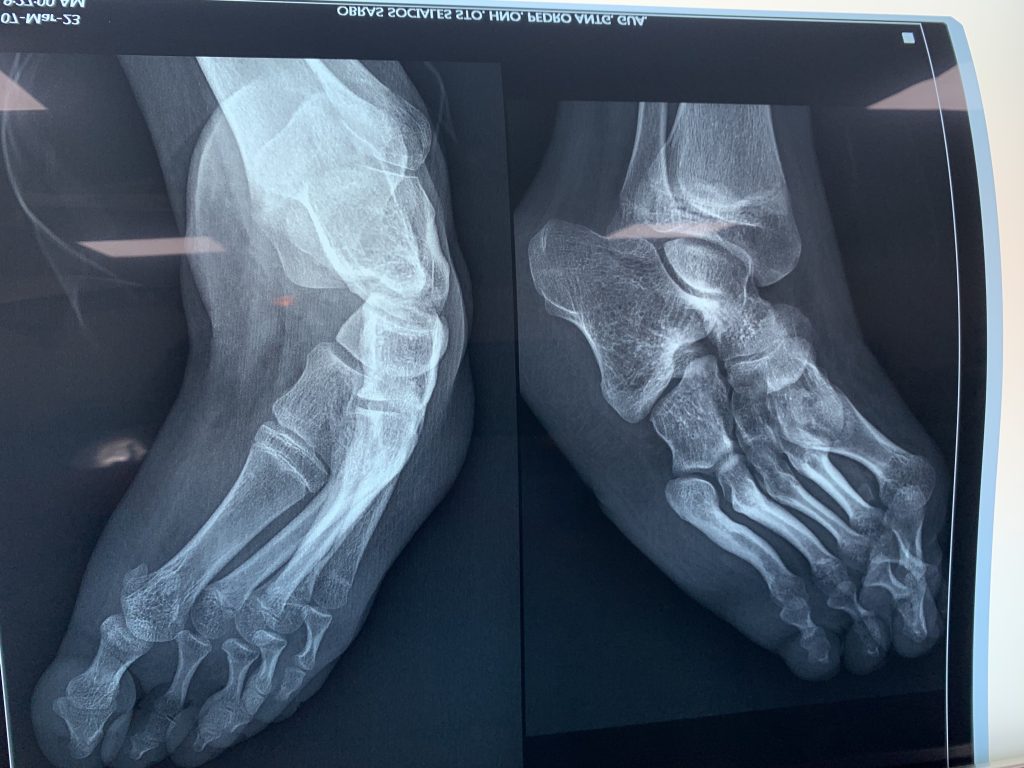

An 11 year-old girl, Sealy, was born with club foot that has developed into a severe deformity on her right side. She has had two prior surgeries, one at 18 months and one at 4 years to attempt to correct the club foot with very little success. Since that time she has been living with a very painful condition that has brought her social stigma along with the more obvious physical constraints. Dr. Herbst and Dr. Knecht were able to perform a major correction to her right foot and she currently has a cast that will allow her body to hold her foot in a more normal position while healing takes place to help her maintain her improved foot position. Sealy and her mother were very grateful to have the procedure and cognizant of how liberating this will be for her life. She will have a more normal childhood during her school years and infinitely improve her occupational potential. Just one more patient who has been profoundly touched by Team Hope in Motion.